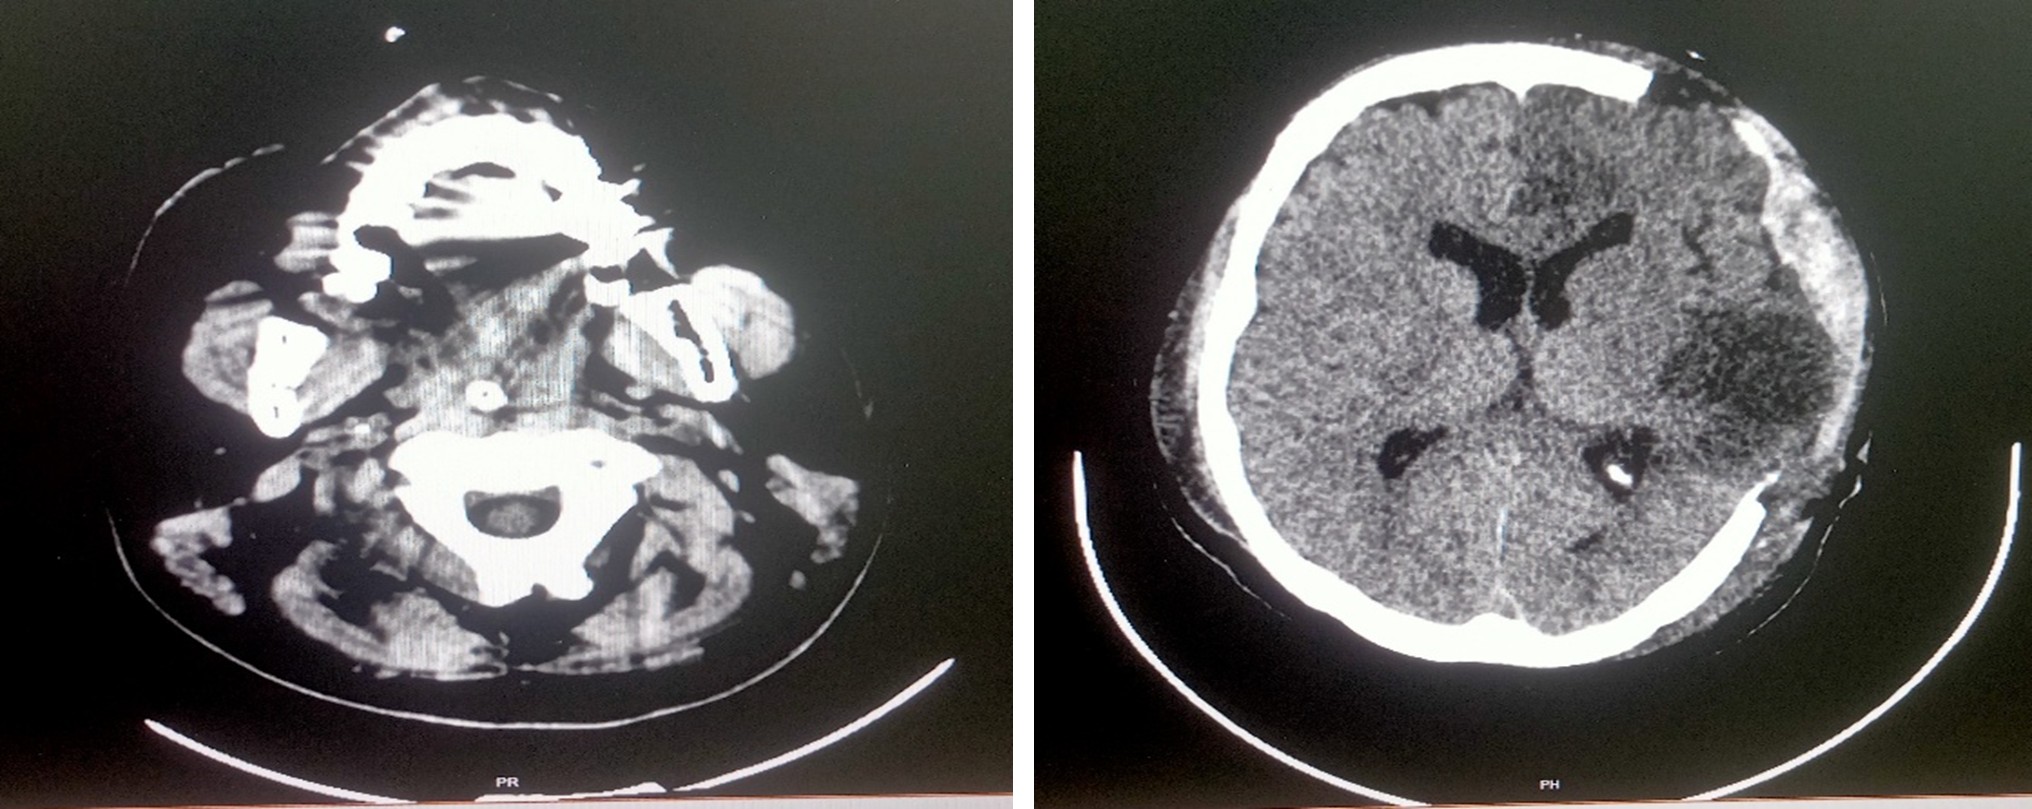

MRI of brain screening – Report 17.06.2025

The acute infarct left MCA territory with minimal mass effect

Multislice CT scan brain plain study – 17.06.2025

Acute infarct in left temporo – parietal cortex with minimal mass effect

Multislice CT scan brain plain study – 18.06.2025

Acute infarct in left MCA and ACA territory with mass effect and midline shift

Multislice CT scan brain plain study – 23.06.2025

Postoperative bony defect left fronto – temporo – parietal region with infarct in left MCA and ACA territory with minimal mass effect

Multislice CT scan brain plain study – 24.06.2025

K/c/o Left ACA and MCA territory infarct status post craniectomy, on follow-up

Subacute infarct with hemorrhagic transformation seen in left frontal parietal and temporal lobes

- Malignant Middle Cerebral Artery (MCA) infarct and surgical decompression: Pre-op and post-op CT brain findings